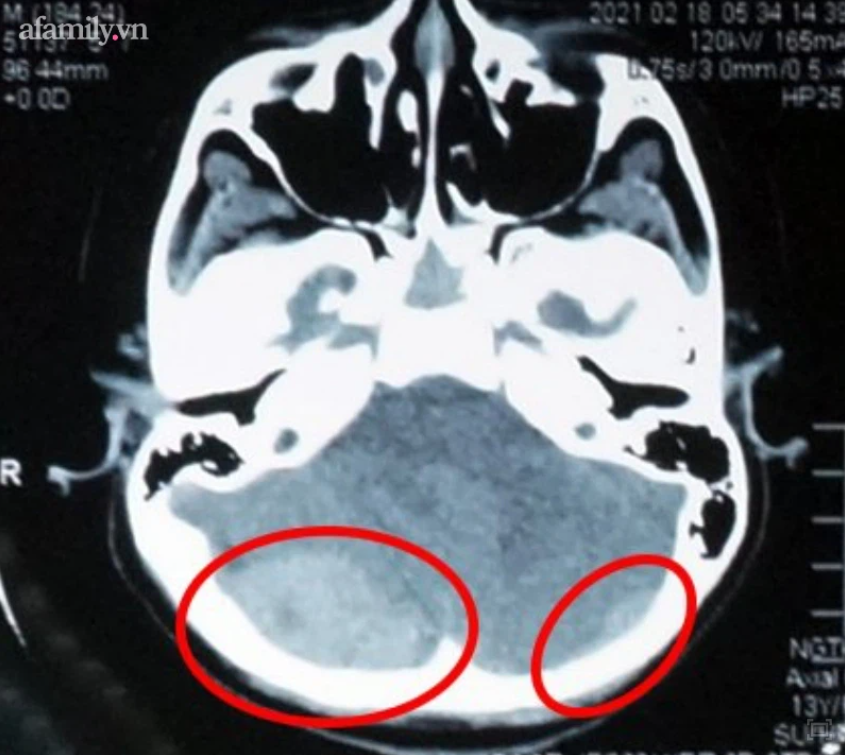

Tại đây dựa trên kết quả cận lâm sàng và chụp CT Scanner, các bác sĩ chuyên khoa Ngoại Thần kinh chẩn đoán em N. bị máu tụ ngoài màng cứng hai bên, xuất huyết dưới nhện dọc liềm não, lều tiểu não hai bên, dập não vùng trán nền hai bên, nứt sọ vùng chẩm hai bên.

Tiếp tục được tiến hành chụp CT-Scanner sọ kiểm tra, kết quả cho thấy tình trạng máu tụ bắt đầu tăng lên đáng kể, diễn biến đe doạ tính mạng bệnh nhân nên các bác sĩ giải thích tình trạng cho gia đình và quyết định phẫu thuật cấp cứu cho bé.

Dưới sự hỗ trợ của các thiết bị hiện đại, các bác sĩ tiến hành mở sọ giải áp lấy máu tụ, giải phóng chèn ép não vùng hố sau bên phải và cầm máu bằng các vật liệu chuyên dụng với thời gian nhanh nhất.